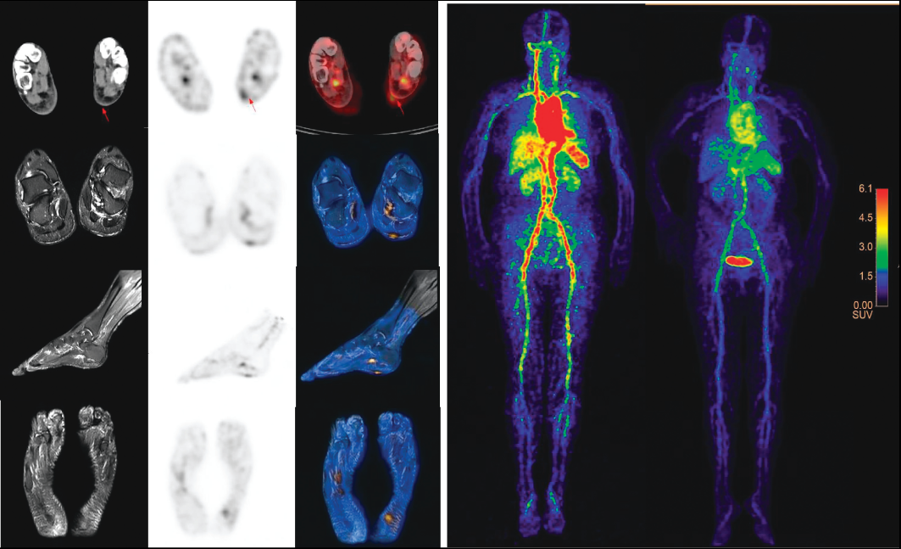

4. 针对肿瘤免疫治疗(抗PD-1治疗)优势患者筛选及疗效评价挑战,研制出新型固体靶核素124I,优化出室温条件60秒快速、原位标记单抗技术,实现基于我国NMPA批准的首个抗PD1治疗药物(JS001, 特瑞普利单抗)的直接放射性标记的临床研究。相关成果以Positron Emission Tomography Imaging of Programmed Death 1 Expression in Cancer Patients Using 124I-Labeled Toripalimab:A Pilot Clinical Translation Study为题,于2021年5 月发表在Clinical Nuclear Medicine 杂志上。

图4: I-124标记PD1单抗的PET 临床转化

4. Shujing Wang†, Hua Zhu†,*, Jin Ding, Feng Wang, Lixin Ding, Yan Zhang, Nan Li, Sheng Yao, Xinan Sheng*, Zhi Yang*. Positron Emission Tomography Imaging of Programmed Death 1 Expression in Cancer Patients Using Iodine-124 Labeled Toripalimab: A Pilot Clinical Translation Study. Clinical Nuclear Medicine, 2021, 46(5), 382-388.